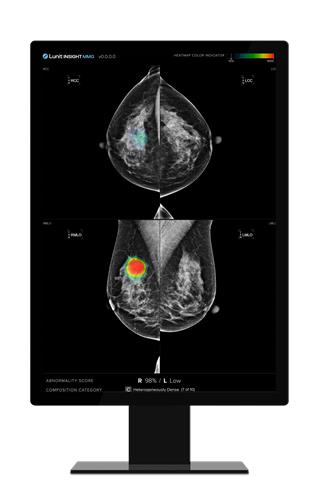

루닛 인사이트 MMG는 AI를 기반으로 유방암을 검출하는 제품이다. 의심 부위의 위치 정보와 수치로 계량화한 의심 정도를 제시해 의료진의 진단을 돕는다고 회사는 설명했다.